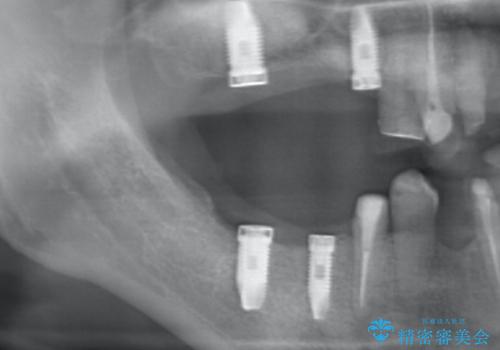

- これまで悪くなっては歯医者に通い、その都度治療を受けてきたがどんどん悪くなる痛くてしっかりと噛めない、これを機にしっかりと噛めるような治療を受けたいと希望され来院されました。

保存不可能な歯の抜歯→インプラント治療、根管治療、精密なセラミッククラウンの製作を行い長期的に安定し、審美的で機能的な治療を計画します。

歯が悪くなるたびにその都度治療を行うと、付け焼き刃の治療となりやすくまた横の歯が悪くなってしまった場合に再治療が必要となったり延々と治療が続くことがしばしばです。

隣接する歯や、残すことのできない歯をインプラントにしっかりと置き替えていくことで安心して長期にしっかりと噛める口腔内環境を達成することができます。